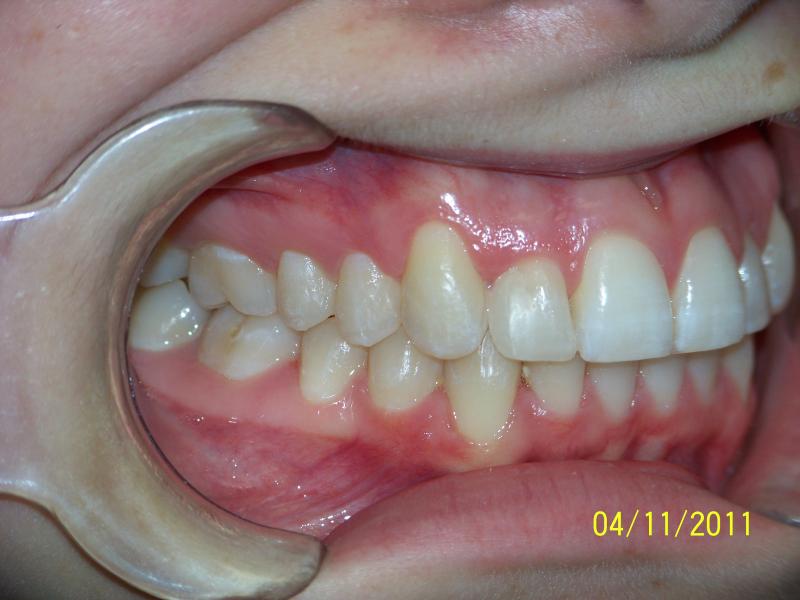

INVISALIGN, 10 months, 1 series of aligners to correct alignment, deep overbite and shift teeth to the right to match upper and lower mid line, TOTAL TREATMENT TIME: 10 months COSMETIC DENTISTRY: incisal reduction of anterior teeth before and after Invisalign.

Deep Overbite, Teeth Reshaping, Testimonial